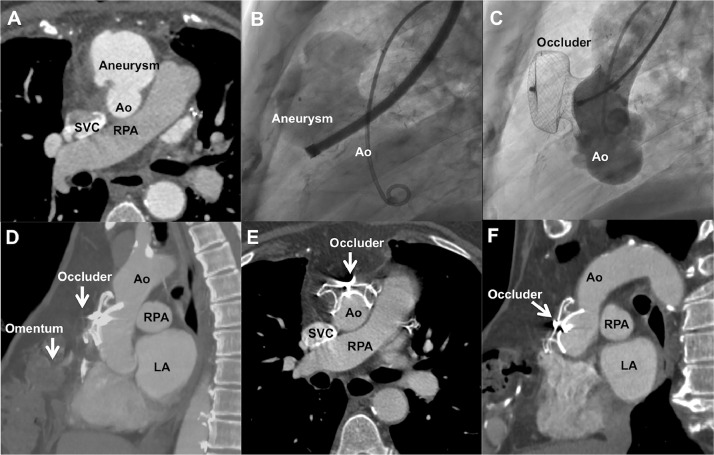

Fig. 1.

Recurrent aortic pseudoaneurysm. Recurrence after bovine pericardial patch repair of ascending aortic (Ao) pseudoaneurysm with sternal debridement and omentoplasty is shown in axial computed tomography (A). Angiogram from a large sheath advanced from the left brachial artery delineates the large pseudoaneurysm from the anterior wall of ascending aorta (Video 1) on lateral view aortogram (B) that is closed by an atrial septal occluder (C). Sagittal (D), axial (E), and long-axis (F) computed tomography images after 30 months confirms complete closure. LA, left atrium; SVC, superior vena cava; RPA, right pulmonary artery.